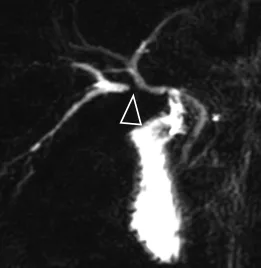

A

B

Figure 15. Chez ce patient chez qui on recherche des signes de CSP, une image lacunaire (A, tête de flèche) pourrait faire évoquer une sténose du canal hépatique commun. Cependant, cette image piège n’est en réalité pas pathologique. La topographie, le caractère extrinsèque et les bords parallèles rectilignes de cette « lacune » sont très caractéristiques : une acquisition complémentaire (séquence « à l’état d’équilibre ») confirme qu’il ne s’agit que d’une image d’empreinte artefactuelle liée au passage de la branche droite de l’artère hépatique (B, tête de flèche).